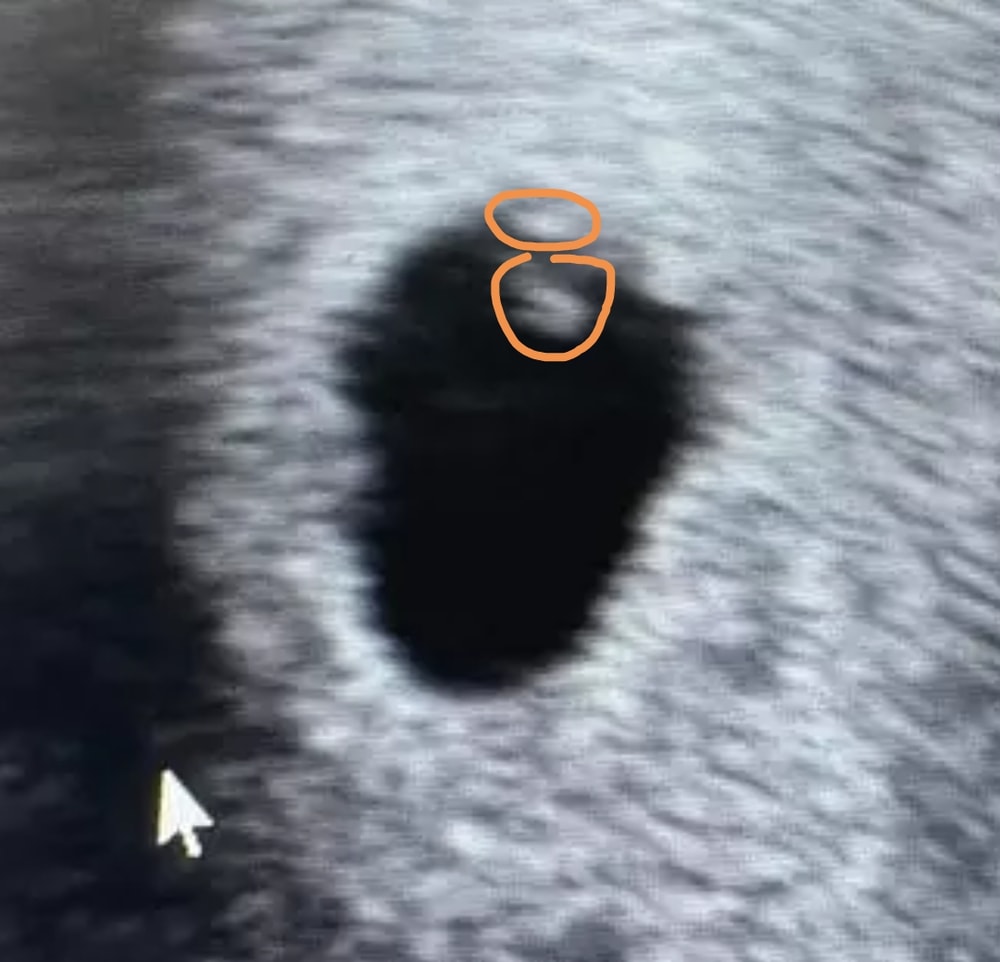

А я вижу и эмбрион, и ЖМ, но могу ошибаться. У подруги в 5,3 тоже так же было. Сверху эмбрион, ниже ЖМ

Это не эмбрион, а желточный мешочек. Но то, что он появился, - хороший знак. Значит, скоро появится эмбрион.